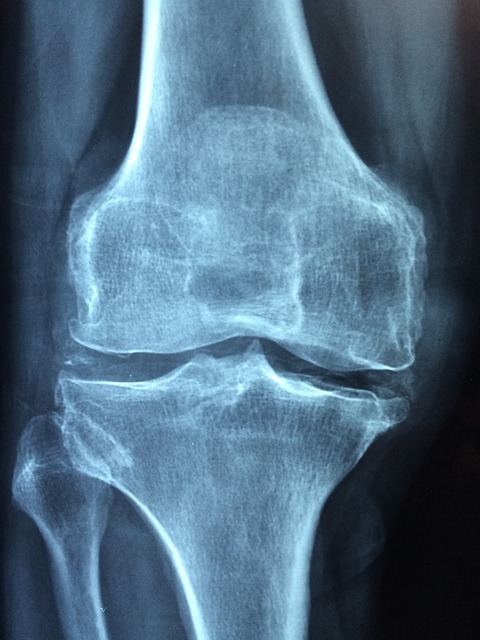

골다공증은 뼈 관련 질환 중 하나로, 뼈의 밀도와 질이 감소하여 뼈가 취약해지는 만성 질환입니다. 이러한 변화로 인해 뼈가 얇아지고 약해져서 더 쉽게 부러질 수 있고, 일상생활에서의 활동에 제약을 받을 수 있습니다. 이 질병은 주로 노화로 인해 발생하지만, 뼈 손실을 조절하지 않으면 젊은 성인들에게도 영향을 미칠 수 있고, 발생 가능성이 있습니다. 골다공증은 주로 뼈의 밀도 감소와 미세한 뼈조직의 변화로 설명됩니다. 뼈의 밀도는 골다공증 환자에서 정상 뼈에 비해 낮으며, 이로 인해 뼈가 더 쉽게 부서질 수 있습니다. 그 결과로 골다공증 환자는 일상 활동에서 골절 위험이 크게 높아지며, 특히 골반, 요추, 대퇴, 손목 등 다양한 부위에서 골절이 발생할 수 있습니다. 골다공증은 노화 과정과 밀접한 관련이 있습니다. 노화로 인해 성인의 뼈 밀도는 감소하고 뼈의 품질이 저하됩니다. 이것은 노화하는 인구에게 심각한 문제가 되며, 특히 여성들 사이에서 빈발합니다. 이 질병은 골절이 생기면 통증이 생기고, 골절이 발생한 부위에 따라 다양한 증상이 나타날 수도 있지만 대개 무증상으로 진행되며, 환자들이 문제를 느끼는 경우가 드뭅니다. 따라서 골다공증을 심각하게 여겨야 하며, 골다공증 예방 및 치료는 중요한 과제 중 하나로 인식됩니다. 뼈 건강을 유지하고 노화로 인한 골다공증의 위험과 뼈 손실을 최소화할 수 있습니다.

골다공증은 노화 및 뼈 밀도 감소하고 약해지는 질병으로, 골절과 뼈의 손상 위험이 높아집니다. 골다공증의 효과적인 치료는 뼈 건강을 회복하고 유지하기 위한 매우 중요한 단계입니다. 골다공증의 치료 옵션과 관련 정보에 대해 함께 알아봅시다.